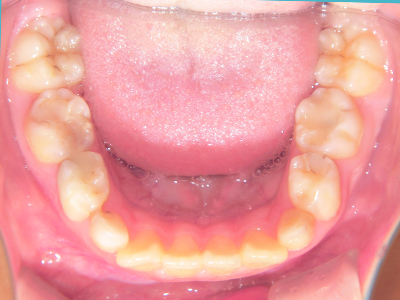

ないき歯科クリニックでは、上あごの成長不足を補い、鼻呼吸を獲得しつつ歯列を整え、将来のお口をより健康な状態にすることをゴールに定める矯正治療をおこなっています。